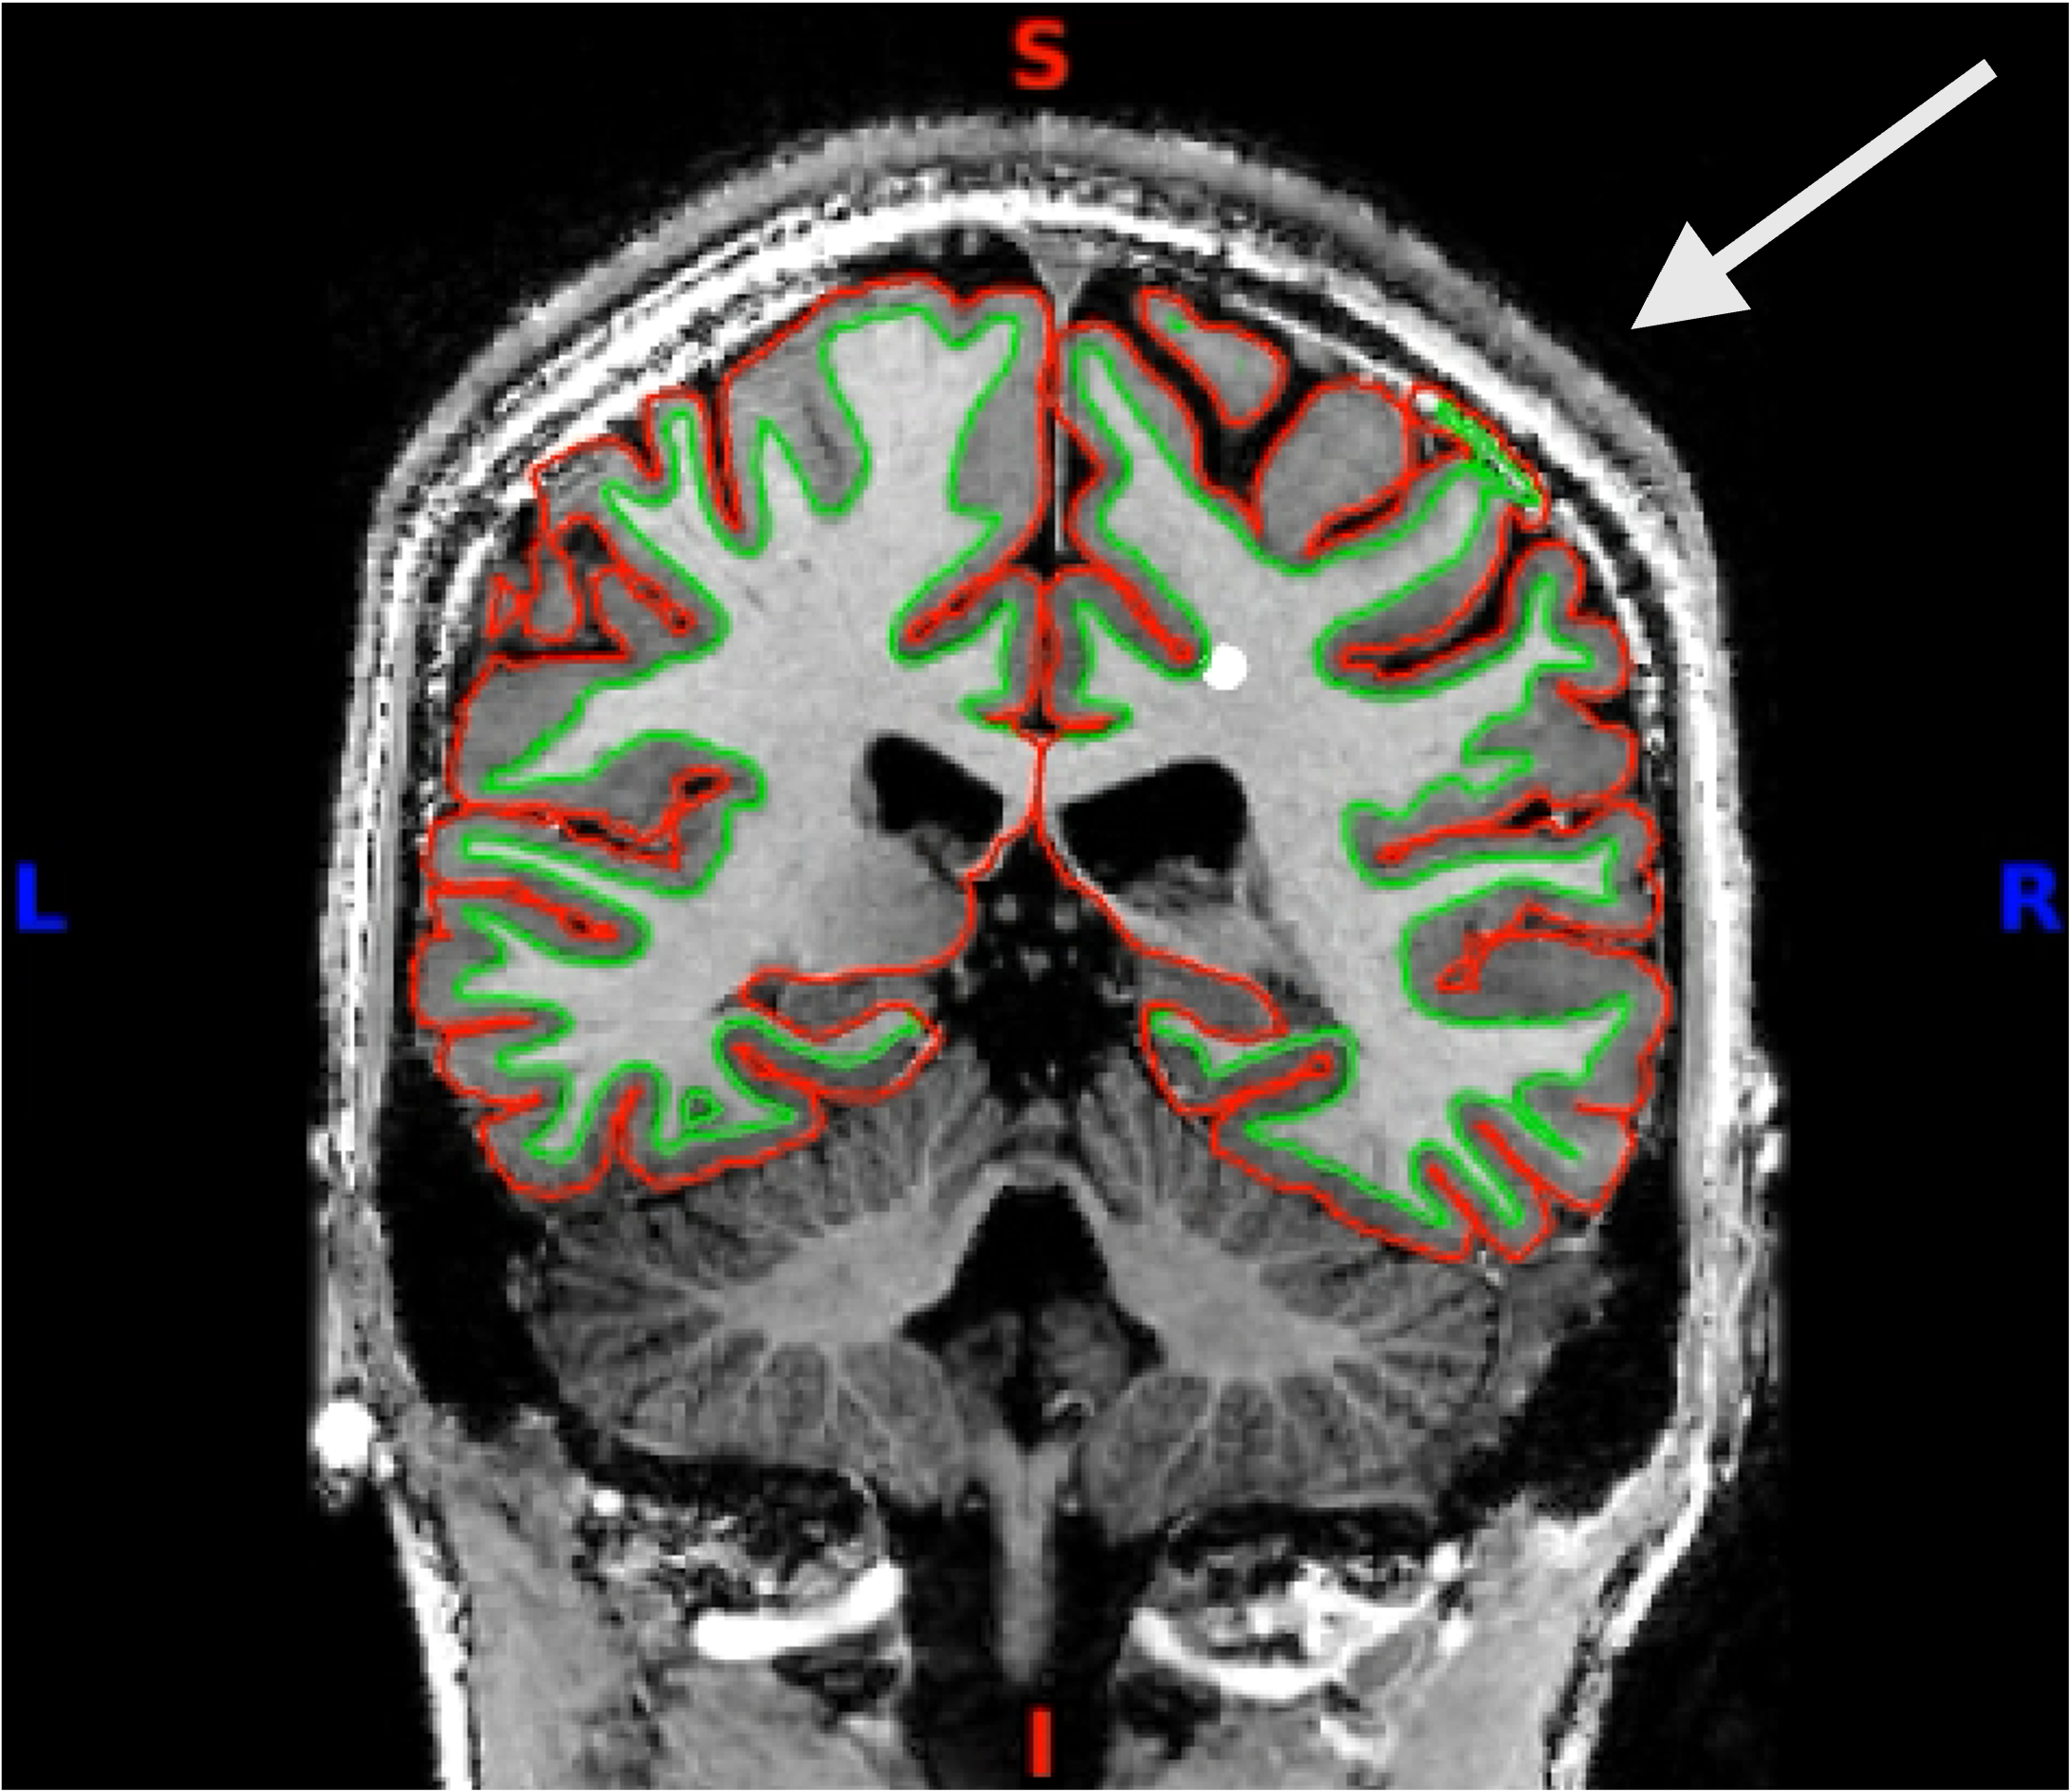

You can click through the volume and see if you spot any faulty reconstructions. In the below example, the right hemisphere has been misconstructed. Both white and pial surfaces are going into the skull on the right side. This will lead to wrong projections of the functional data - in this case, there was a chunk of ‘NaN’ values in the superior right hemisphere.

Here you can see it more closely: